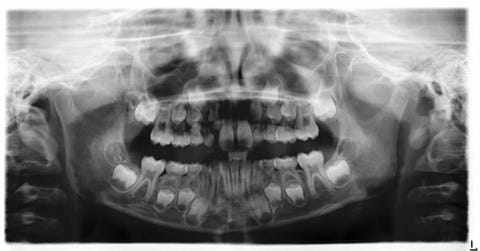

Wanneer moet je kiezen trekken of verstandskiezen trekken?

Kiezen trekken gebeurt vaak als ze beschadigd of ontstoken zijn.

Verstandskiezen trekken is vaak preventief, bijvoorbeeld als er onvoldoende ruimte is in de kaak of ze scheef groeien. Beide ingrepen worden uitgevoerd door een gespecialiseerde tandarts en orthodontist.